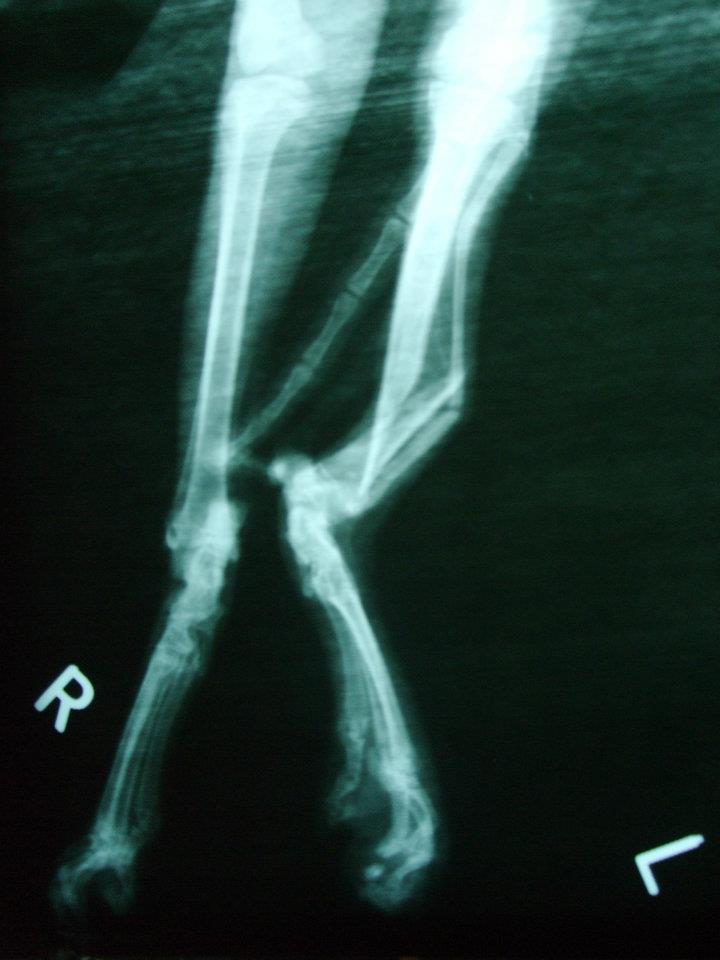

主題: 下顎、腿多處骨折的蜘蛛人 申請者姓名: 岳丹楓 花色: 申請日期: 2012-07-15 12:45:03 申請者部落格: 申請者臉書網址: 所在縣市/合作醫院: 台北市/澄毅動物醫院 治療費用: 4800元 需求人數: 12人 已結案 (2013-06-27 13:22:09) 報名人員: Bei Bei Wang(已付款)、Bei Bei Wang(已付款)、陳比比(已付款)、Ru Shiuan Liu(已付款)、SY Liou(已付款)、SY Liou(已付款)、牡羊先生(已付款)、Pomelo Peng(已付款)、Pomelo Peng(已付款)、orange liu(已付款)、Ku-ai Gina Chen(已付款)、艾薇拉、Kent、Athena Athena Tzeng、sally(已付款)、 候補人員: Patty Chen、julie lee、小P、 動物病情說明: 岳姊通報:陳小姐在龍門里捕捉or拾獲貓咪,嘴巴無法閉合行走姿勢怪異,送至醫院X光檢查發現腿部多處骨折、下顎骨折無法進食,插鼻胃管灌食,上點滴維持體力。